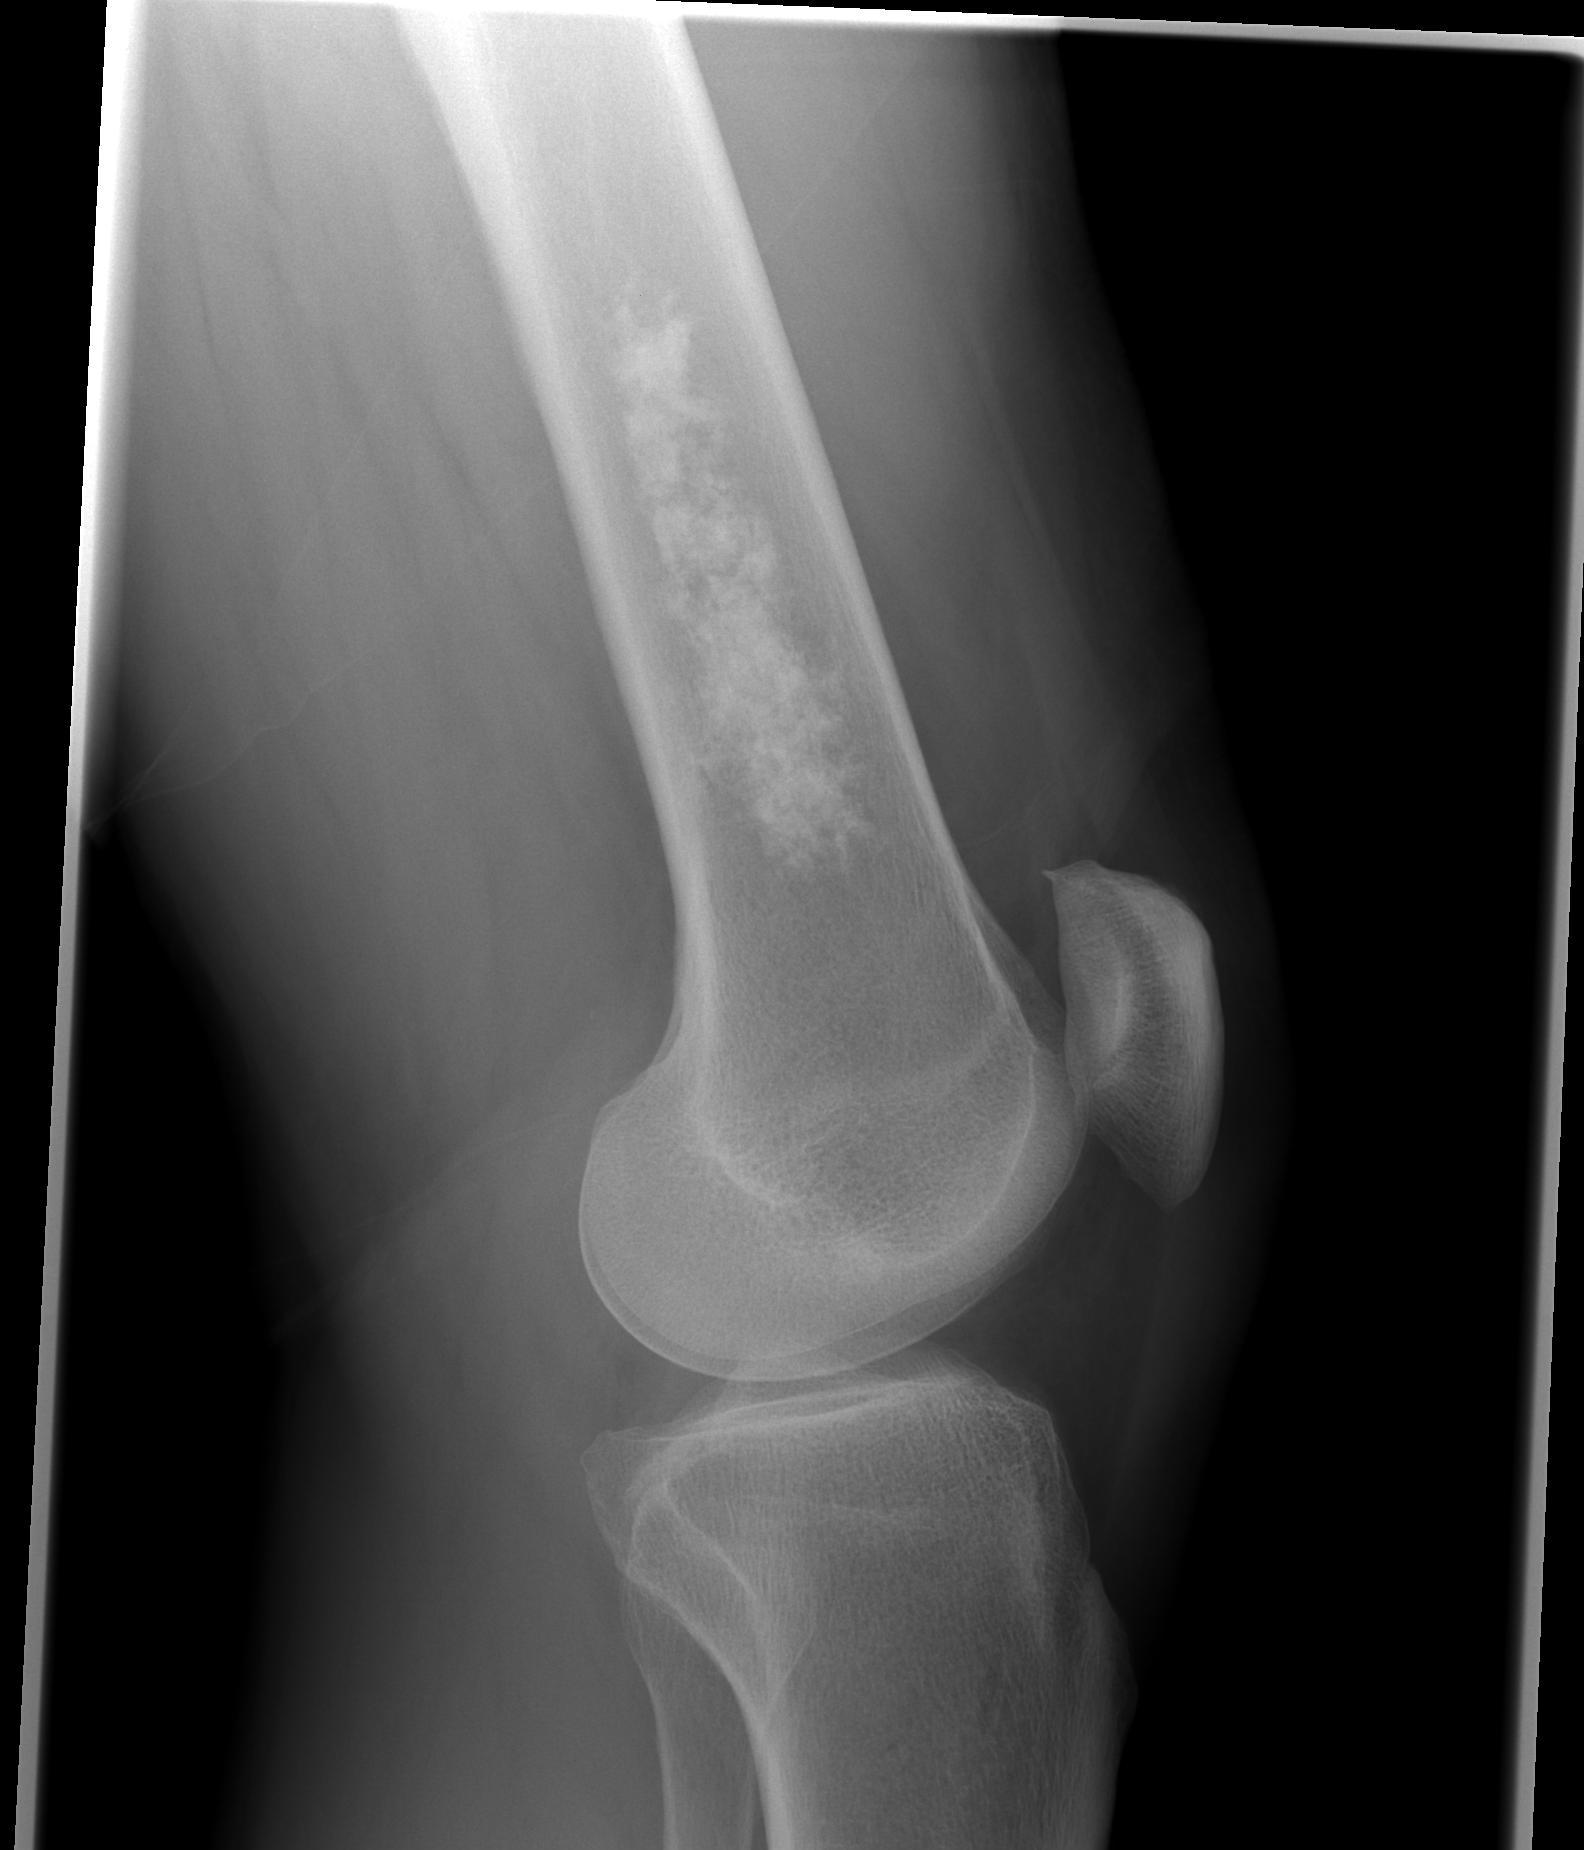

X-ray

Intralesional calcification - punctate, stippled calcification and broken rings

Differential diagnosis long bone with intralesional calcification

1. Enchondroma

2. Bone infarct

3. Chondrosarcoma

Large, central enchondroma